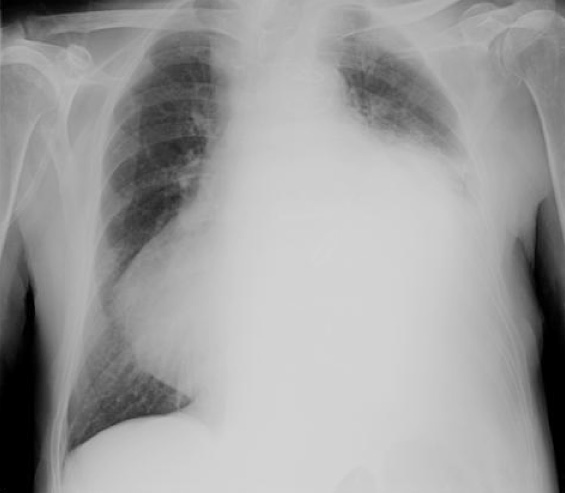

L’Rx torace rilevava cardiomegalia, aortosclerosi e versamento pleurico sinistro (Figura 3).

Figura 3. Rx torace (aprile 2012) che mostra cardiomegalia, aortosclerosi, versamento pleurico sinistro